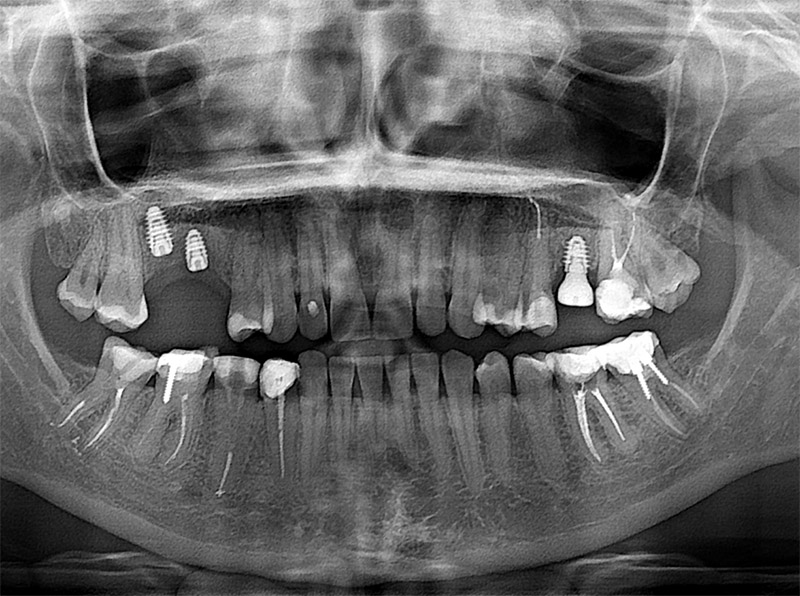

Пациент много читал об имплантации зубов, но было и много сомнений. Провели 3Д рентген обследование. Было предложено 2 варианта лечения. Пациента напугала полная стоимость лечения. Обсудив с пациентом все плюсы и минусы обоих вариантов, выбрали понятный и приемлемый по срокам и стоимости вариант.

Февраль. Установка имплантов

Выполненные манипуляции:

- Анестезия + премедикация - 2 300 ₽;

- Вкручивание в верхнюю челюсть 3 имплантов Osstem (Корея) - 3 × 31 000 ₽;

- Установка в имплант формирователя десны - 3 × 4 950 ₽;

- Наложение швов - 6 × 250 ₽;

Итого: 11 650 ₽

Расстаемся с пациентом на 4 месяца до полного приживления имплантов